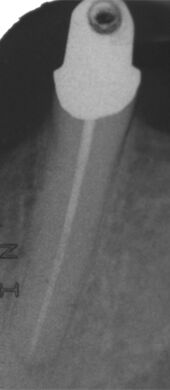

Erfolgreich abgeheilte Entzündung 6 Monate später. Beschwerdefreier Zahn.